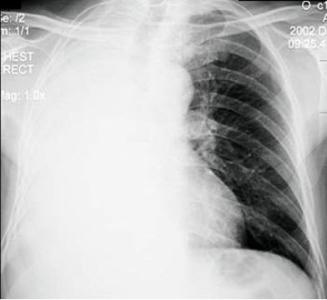

间质性肺炎x片

间质性肺炎x片,

急性间质性肺炎

间质性肺炎[病例帖]

淋巴细胞间质性肺炎~lip

间质性肺炎e.大叶性肺炎男._考试资料网

精彩幻灯:特发性间质性肺炎病例分享